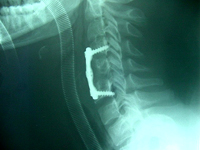

El tipo de tratamiento más indicado para cada lesión dependerá, esencialmente, del tipo de fractura y de la presencia de lesión neurológica. Otros factores a tener en cuenta son la edad y las expectativas del paciente. El tratamiento conservador, habitualmente, consiste en colocar un corsé rígido (de yeso o de plástico) durante unos tres meses. El tratamiento quirúrgico se basa en practicar una fijación interna intentando corregir la vértebra deformada y obtener una estabilización sólida.